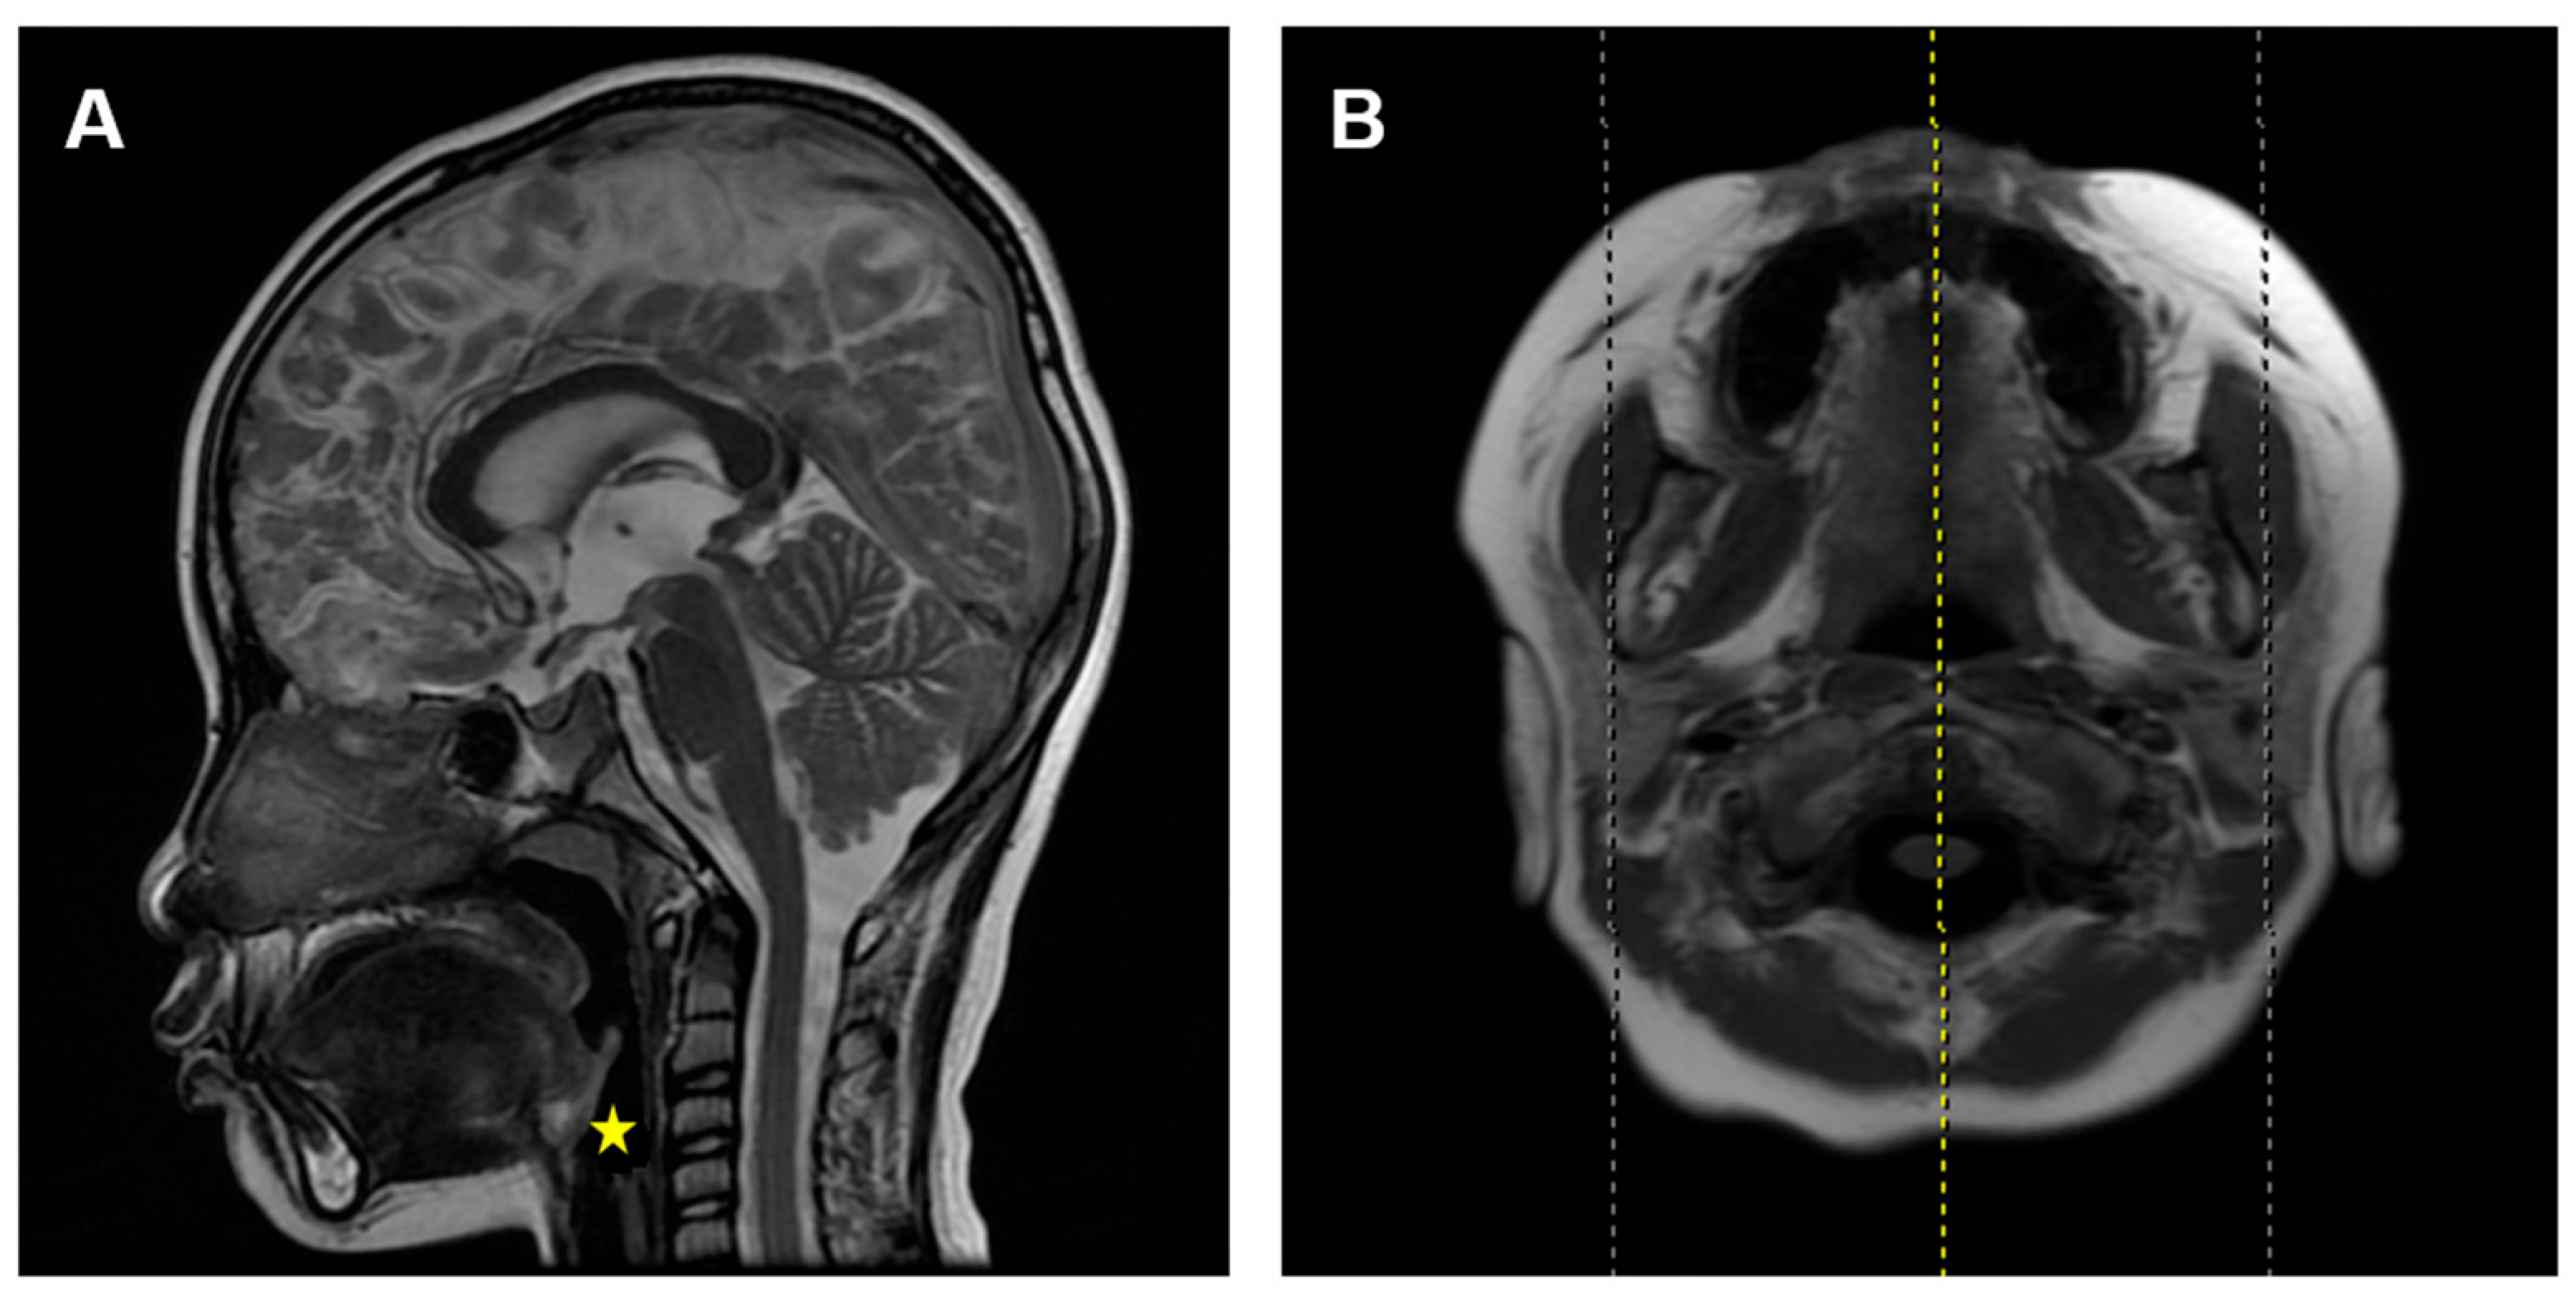

Figure 1. Mid-sagittal and cross-sectional head MRI images in T2W1 signal. (A) Mid-sagittal image. (B) Cross-sectional image. The yellow line represents the cross-sectional cutting position of the yellow star.

According to a previous study [15], the inclusion criteria were set as: (1) children who underwent MRI for reasons such as head trauma, febrile seizures, or suspected intracranial lesions, with no facial abnormalities other than adenoid hypertrophy, like nasal septum deviation, nasopharyngeal tumors, sinusitis, maxillary sinusitis, or delayed brain development; and (2) children with clear and complete mid-sagittal head MRI images in T2W1 signal (Figure 1).